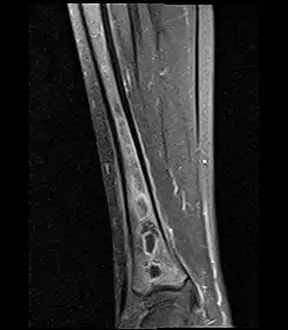

Sagittal T1-weighted fat-suppressed post gadolinium image showing the extent of the multiloculated intramedullary abscess.